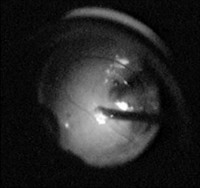

After standard three-port pars plana vitrectomy (Storz Premier) and separation of posterior hyaloid face from the underlying retina intranasaly to the optic disk (Fig. 1) delimination was carried out using infusion of perfluorooctane (Dk-line Perfluorodekalin, Bausch & Lomb) liquid between tough posterior hyaloid and underlying retina using 20 gauge cannula attached to a syringe (Fig.2).

| Fig. 1 | Fig. 2 |